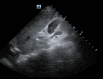

Point-of-care ultrasound is increasingly important in the management of acute medical emergencies. An elderly man was brought to the emergency department after 2 days of fever and urinary retention. He was drowsy and had peri-arrest arrhythmia. He was hypoperfused peripherally with a systolic blood pressure of 45 mmHg and so was managed as for septic shock with no obvious aetiology. Chest and abdominal physical examinations were unremarkable. The source of sepsis was unclear. A point-of-care abdominal ultrasound was performed by the reviewing internist which detected a pneumoperitoneum, leading to a change in diagnosis to a perforated viscus which was confirmed later by a CT of the abdomen and pelvis.

Learning points: Pneumoperitoneum leading to septic shock is a medical emergency, but diagnosis is frequently delayed as the physical examination and chest and abdominal x-rays may fail to detect the condition in the critically ill patient, leading to delayed medical and surgical intervention.There is a role for point-of-care abdominal ultrasound for the early diagnosis of pneumoperitoneum with the air reverberation artefact.Point-of-care ultrasound of the abdomen to identify intra-abdominal air is an important physical examination adjunct in undifferentiated septic shock and should be incorporated into the routine care of patients and included in the acute medicine training syllabus.